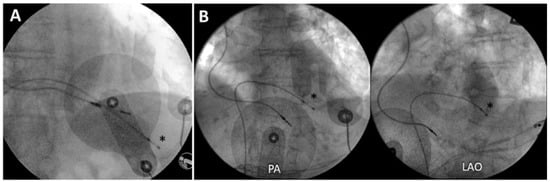

Transvenous pacing